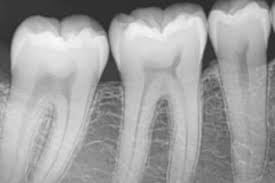

La radiografía apical se realiza con pequeñas placas radiográficas que se colocan dentro de la boca y se exponen mediante un equipo de rayos X externo.

Antiguamente, estas radiografías debían revelarse manualmente, pero hoy en día se utilizan dispositivos intraorales digitales con sensores que permiten obtener la imagen de forma inmediata en pantalla.

Este avance ha hecho que el proceso sea más rápido, preciso y cómodo.

Las radiografías intraorales periapicales se realizan para observar el diente completo, incluyendo la corona, la raíz, el ápice, el tejido óseo circundante y el espacio periodontal, con el fin de detectar lesiones no visibles a simple vista.

Aunque una radiografía panorámica suele ser suficiente para la mayoría de los diagnósticos, en algunos casos se requiere una radiografía periapical para mayor detalle.

• Diagnosticar caries dentales, identificando si afectan al esmalte, la dentina o la pulpa dental.

• Detectar caries interproximales (entre dientes) de forma preventiva.

La radiografía periapical es una técnica fundamental en el diagnóstico bucodental, permitiendo evaluaciones precisas y tratamientos más efectivos.